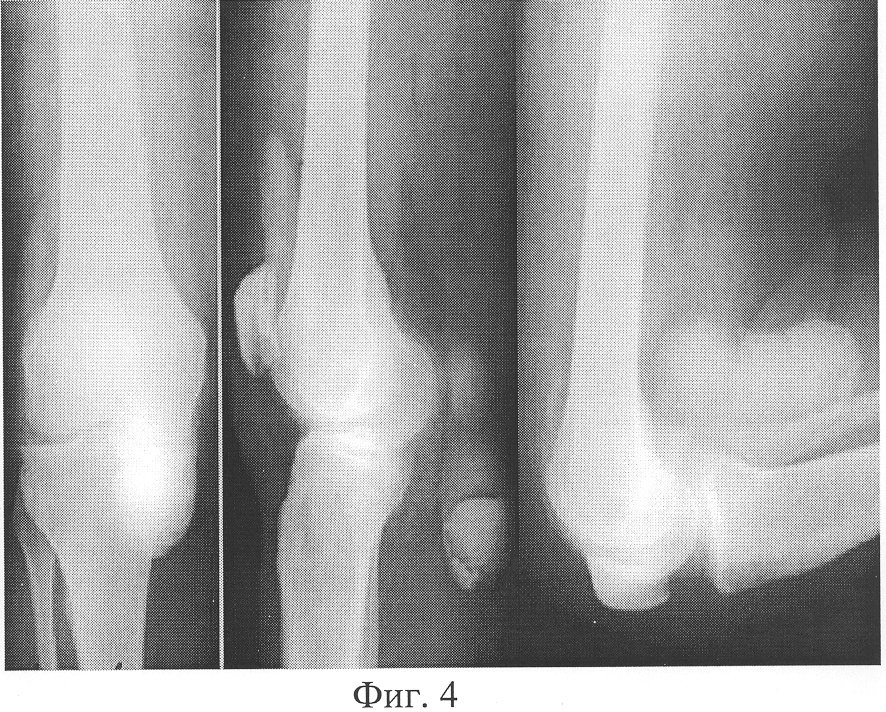

Фиг.6 – рентгенограммы конечностей в отдаленные сроки.

На контрольном осмотре справа через 2 года, слева через 1 год ось конечностей правильная, ходит без дополнительных средств опоры, болей в суставе практически нет. Функция суставов – полная (Фиг.6). По данным ультразвукового метода исследования в подколенной области кист нет.